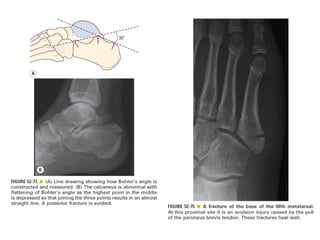

Skeletal trauma was presented by Dr Laith Fadhel with reference to Grainger's Diagnostic Radiology textbook. The presentation covered skeletal trauma as assessed through diagnostic radiology techniques. Key findings and treatments for skeletal injuries were likely discussed.